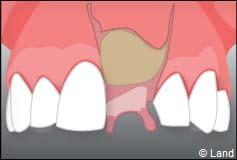

Exemple d’un implant unitaire pour remplacer une dent antérieure manquante.